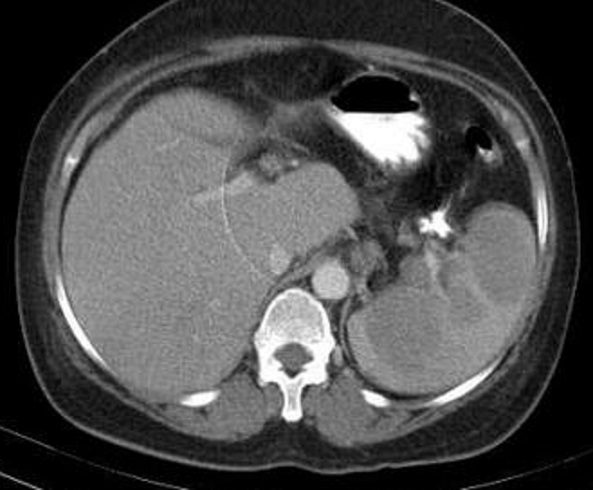

Image radiologique TDM en coupe axial

d'une autre lymphome Hodgkinien maligne de la rate

avec aspect lesionel des nodules ovalaires

hypodensite en rapport de parenchyme de la rate .

Lesions sont en s'observer facile au phase de veine

porte |